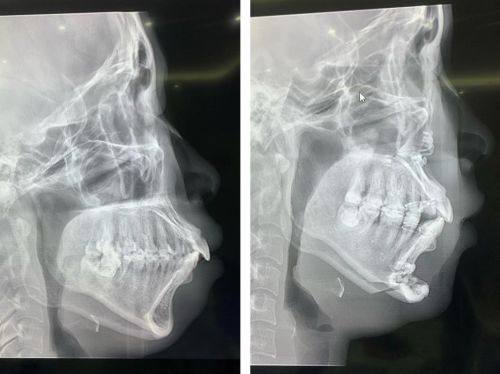

2. 地包天矫正:地包天不仅影响外貌,还会给患者的咀嚼和发音带来不便。尹泰镐院长针对地包天的矫正,会精良行详细的检查和诊断,确定是牙性还是骨性地包天。对于牙性地包天,通过牙齿矫正就可以有效解决;而对于骨性地包天,则需要结合正畸正颌联合治疗。他会在治疗过程中密切关注患者的情况,及时调整治疗方案,确保治疗成效达到至佳。

2. 患者小张,地包天情况比较重度,影响了他的咀嚼和发音功能。他来到韩国首尔第一整形美容医院找到了尹泰镐院长。尹泰镐院长仔细地分析了他的病情,决定采用正畸正颌联合治疗的方法。在手术过程中,尹泰镐院长操作非常精细,术后修复也特别顺利。小张说:“尹院长真的太厉害了,他的技术让我佩服。现在我的地包天问题得到了解决,咀嚼和发音也都正常了,生活质量大大提高。我真的特别幸运能遇到他。”